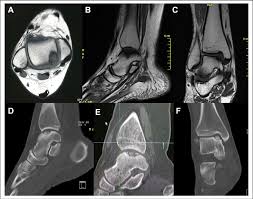

The Radiology Assistant Mri Examination Of The Ankle

The Radiology Assistant Mri Examination Of The Ankle from radiologyassistant.nl

Sprained ankle recovery time varies from case to case. Each test is specifically tailored to your needs. Several pictures may be needed to complete the exam. Indeed, the larger the field of view scanned, the longer time it will take to acquire quality images. Individuals pursue this degree to become radiologist assistants, a more advanced type of radiologic technician with more responsibilities in radiological procedures and patient assessment. Appearance of normal and injured ligaments by kiley d. In some cases, it can take up to 1 hour. Your doctor has recommended you for an mri of your leg.

This is the electric current in the scanner coils being turned on and off. It will be necessary for you to remain as still as possible, however, and some people find this stillness difficult to maintain for the duration of the scan. There are no known harmful effects from the strong magnetic field used for an mri. Long story short, after the protocol of dr. Mris are not typically performed for ankle fractures but may be part of a more detailed examination by an orthopedic surgeon. How long does the mri take? Each picture can take anywhere from a few seconds to fifteen minutes. The mri scanner will make loud tapping noises at certain times during the procedure. Each test is specifically tailored to your needs. Moderate injuries may take between three and four weeks. What does the mri of the foot show? But usually, the result of an mri scan comes within 24 hours and it is also interpreted within 24 hours by a specialized radiologist and similarly,if the result of an mri scan comes within 24 hours, then definitely, those results can help the radiologist in analyzing that who took the test or who ordered for the test of an mri scan. Appearance of normal and injured ligaments by kiley d.

On long te images (like t2) this artifact does also occur but less pronounced. Each test is specifically tailored to your needs. Depending on the severity and complexity of an injury, the ankle mri may take anywhere from about fifteen minutes to half an hour to complete. It will be necessary for you to remain as still as possible, however, and some people find this stillness difficult to maintain for the duration of the scan. Because of limited blood flow to the ligaments of the ankle, more severe injuries may take between three and six months to heal. Indeed, the larger the field of view scanned, the longer time it will take to acquire quality images. The patient should be in a lying position, remain motionless. Each picture can take anywhere from a few seconds to fifteen minutes. From start to end, an mri acquisition can take 15 to 90 minutes. A leg mri also creates pictures of the knee. Appearance of normal and injured ligaments by kiley d. Individuals pursue this degree to become radiologist assistants, a more advanced type of radiologic technician with more responsibilities in radiological procedures and patient assessment. However, if you've done significant damage to the ankle, you could be resting it for a while.